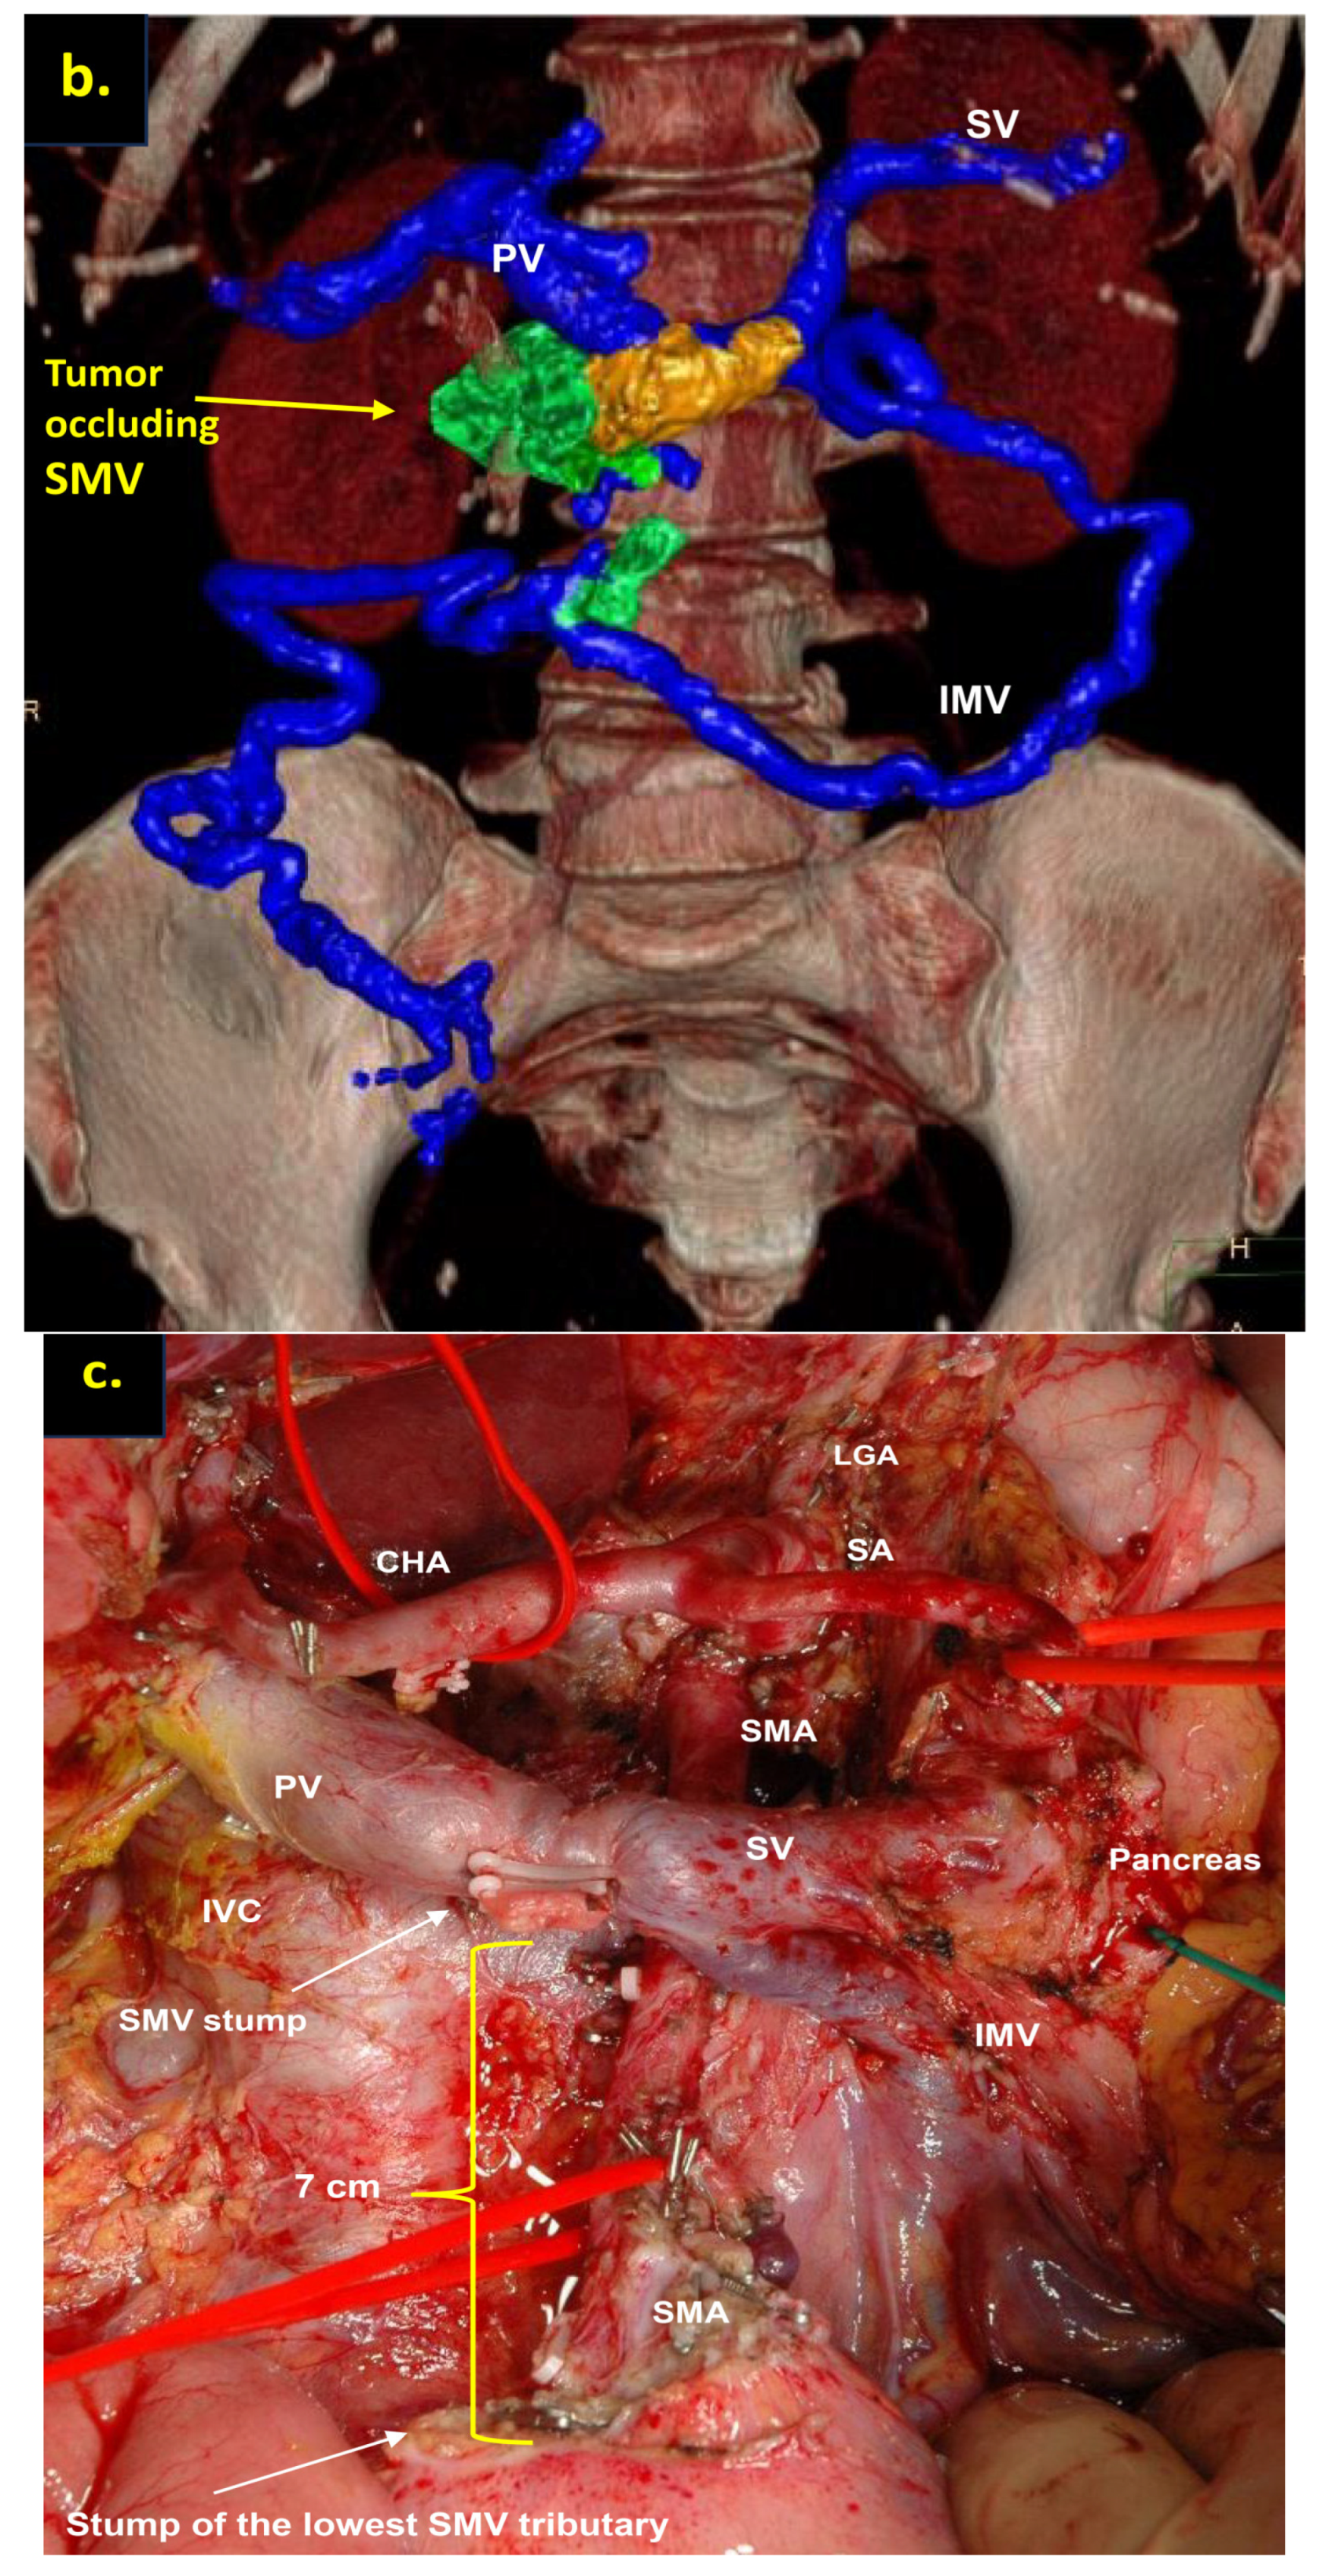

Pancreatoduodenectomy with the SMV and all its tributaries resection without reconstruction for the uncinate PDAC in 64-year-old male. On CT the tumor invades the SMV, which is occluded, the SMV-SV confluence is preserved, and the IMV collaterals are well-developed with dilated intestinal veins, without right-sided vein collaterals and varices. (a) Three-dimensional MIP and (b) three-dimensional VR reconstructions show the dilated SMV tributaries, gastro-epiploic venous arcade, and IMV flowing into the SV; (c) the picture of the operating field after the extended Whipple procedure with the SMV and all its tributaries resection without reconstruction. CHA—common hepatic artery, IVC—inferior vena cava.

Total pancreatectomy with the SMV and all its tributaries resection with resection of IMV and its transposition into SV stump, combined with SMA resection and reconstruction for the uncinate PDAC in 71-year-old female. On CT the tumor invades the IMV and SMV (the last one is occluded), the SMV-SV confluence is preserved, and the IMV collaterals are well-developed with dilated intestinal veins, without right-sided vein collaterals and varices. (a) Three-dimensional MIP and (b) three-dimensional VR reconstructions show the dilated intestinal veins flowing into the IMV, which connects to the SV; (c) the picture of the operating field after the extended Whipple procedure with the SMV and all its tributaries resection without reconstruction. CHA—common hepatic, LGA—left gastric, SA—splenic, RHA—right hepatic, LHA—left hepatic, SMA—superior mesenteric arteries, CA—celiac artery, IVC—inferior vena cava.

Pancreatoduodenectomy with the SMV and all its tributaries resection without reconstruction for the uncinate PDAC in 57-year-old female. On CT the tumor invades the SMV, which is occluded, the SMV-SV confluence is preserved, and the IMV collaterals are well-developed with dilated large collecting intestinal vein, without right-sided vein collaterals and varices. (a) Three-dimensional MIP and (b) three-dimensional VR reconstructions show the dilated large collecting intestinal vein flowing into the IMV, which connects to the SV; (c) the picture of the operating field after the extended Whipple procedure with the SMV and all its tributaries resection without reconstruction. CHA—common hepatic, LGA—left gastric, SA—splenic, SMA—superior mesenteric arteries, IVC—inferior vena cava; (d) the way of the intestinal blood flow after surgery.

In this study, only cases with full excision of SMV trunk and resection of all its tributaries, namely middle and right colic veins, ileocolic trunk, and all the first-order SMV branches (jejunal and ileal), without the reconstruction of above-mentioned vessels, were included. The usual length of the resected SMV with the branches in these cases was 7–8 cm (Figure 5 and Figure 7).

We used different post-processing CT techniques for the assessment of the peripancreatic vessels and collateral venous blood flow adequacy, such as shaded surface display, maximum intensity projection, and 3D volume-rendered (VR) reconstruction imaging. Now, when planning SMV resection with excision of all its tributaries for “low” pancreatic cancer, we consider CT-based 3D-VR reconstruction the best and most necessary option for the depiction of the collateral venous system. Compared to the other rendering CT techniques, VR is superior in delineating vessels, pancreatic parenchyma, the tumor, and adjacent structures (Figure 1a–d, Figure 5a,b, Figure 6a,b and Figure 7a,b,d) [43,44,45].